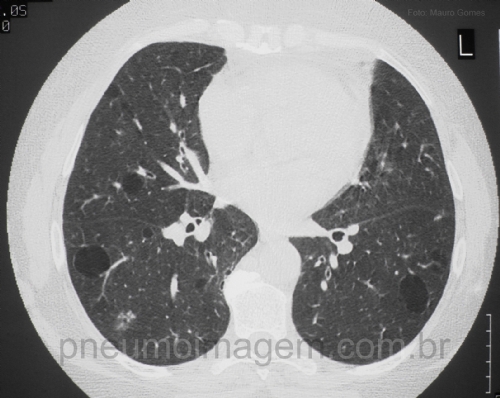

CASO CLÍNICO #7Paciente do sexo feminino, 30 anos, que apresenta dispneia aos esforços e poucos sintomas gerais, além da sensação olho seco. Qual o diagnóstico mais provável? Deixe os seus comentários abaixo!

Female patient, 30, who has dyspnea on exertion and a few general symptoms, and dry eye sensation. What is the most likely diagnosis? Write your comments below!